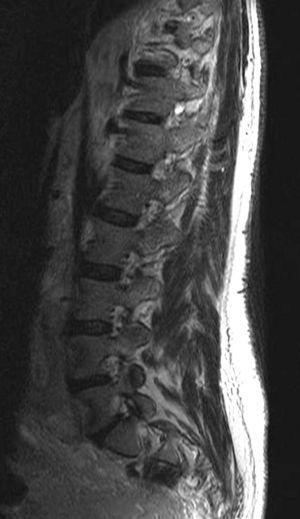

Fig. 3. Resonancia magnética tras contraste intravenoso: (A) sagital línea media y (B) axial. Se aprecia masa retroperitoneal (asterisco) y dilatación secundaria de las venas radiculares. Nótese la deformidad del saco tecal provocada por lipomatosis epidural (flechas).